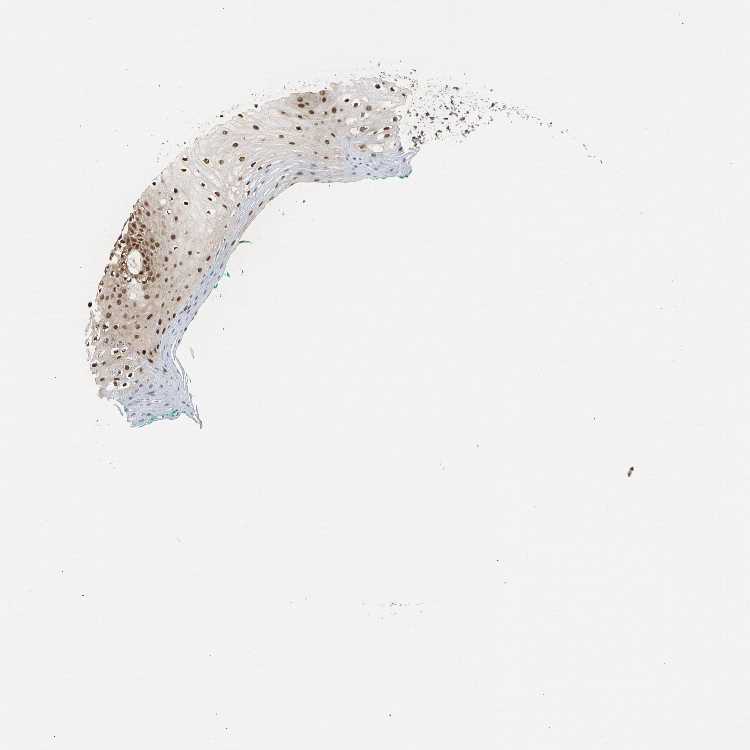

TISSUE PRIMARY DATA ORAL MUCOSA Show tissue menu

ORAL MUCOSA - Antibody stainingi

Antibody staining in the annotated cell types in the current human tissue is reported as not detected, low, medium, or high, based on conventional immunohistochemistry profiling in selected tissues. This score is based on the combination of the staining intensity and fraction of stained cells.

Each image is clickable and will lead to virtual microscopy that enables deeper exploration of all samples and also displays staining intensity scores, fraction scores and subcellular localization as well as patient and tissue information for each sample.

Antibody HPA002561

Squamous epithelial cells Medium